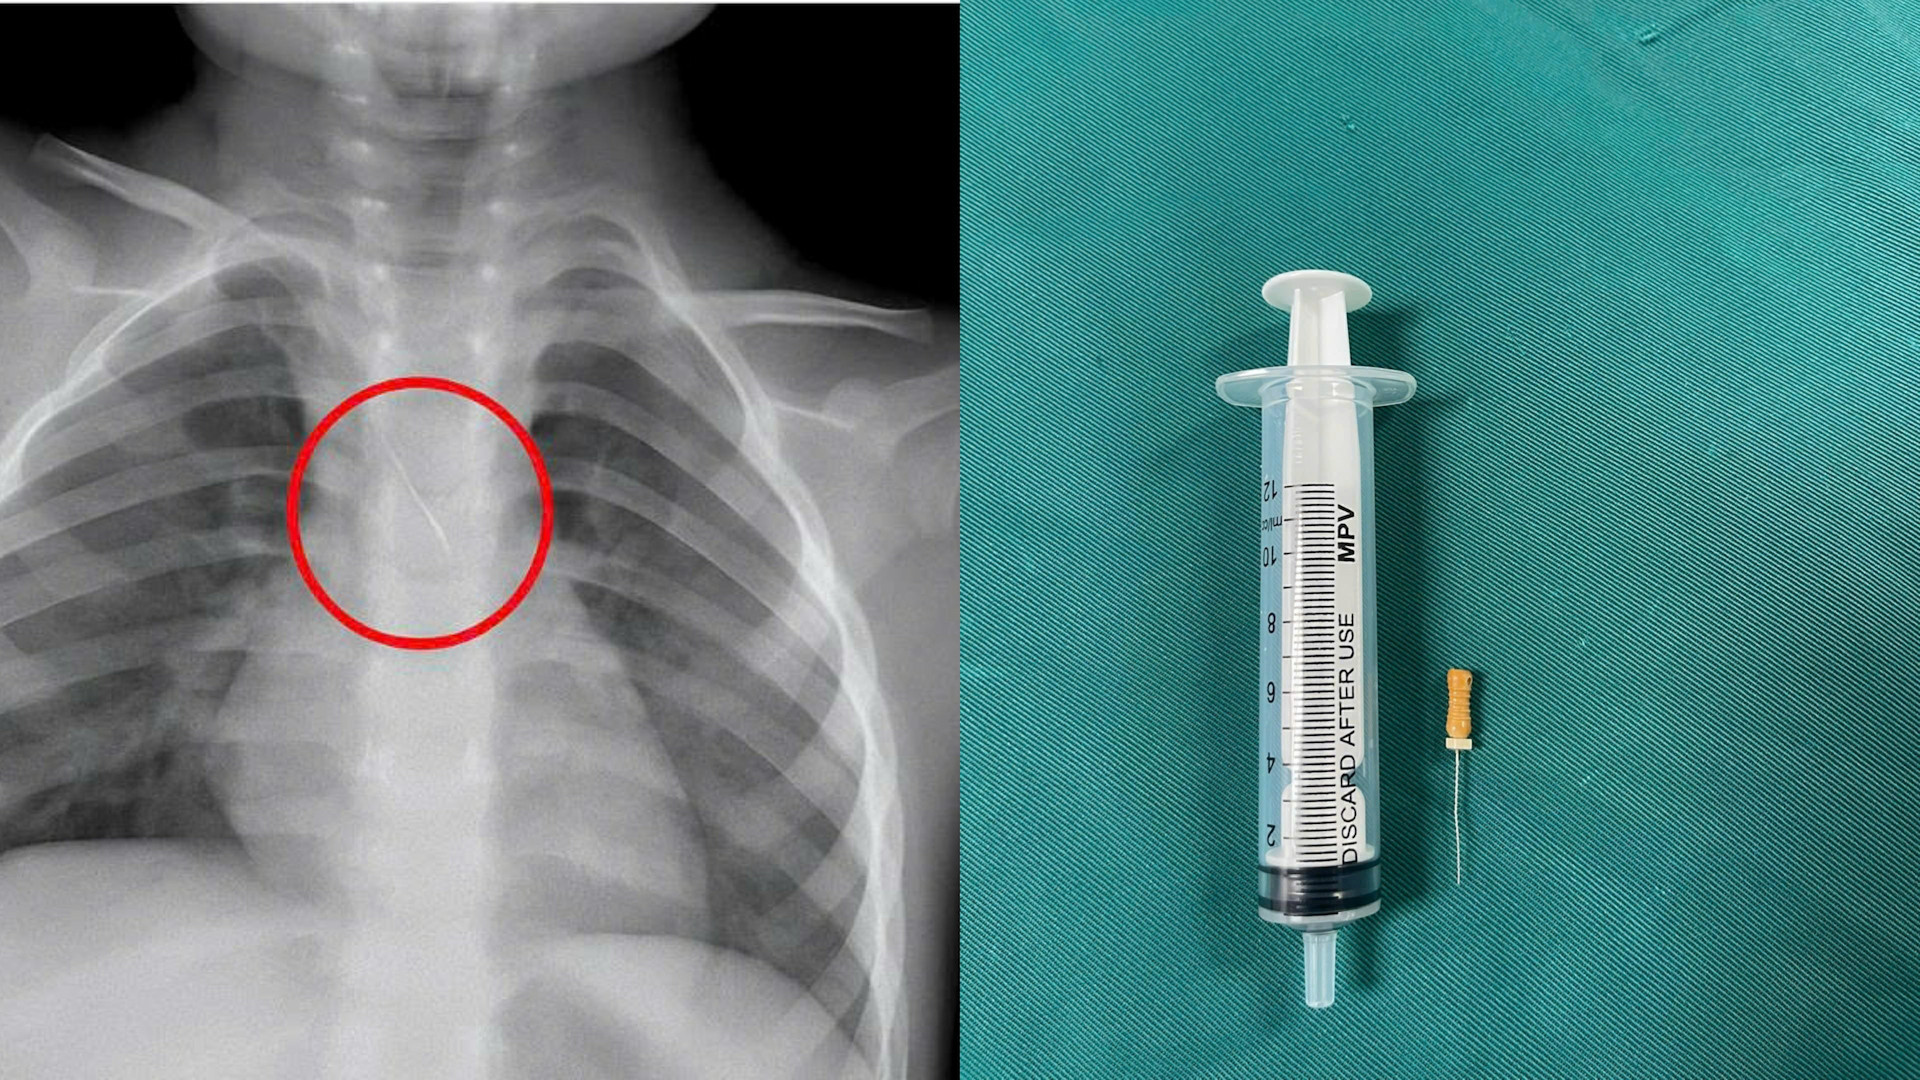

Dị vật này dài khoảng 22mm, nằm ở góc carina (nơi vùng chia đôi khí quản), một đầu nhọn cắm vào 1/3 dưới khí quản, một đầu tròn nằm trong phế quản gốc trái.

Các bác sĩ đánh giá, đây là trường hợp cấp cứu vô cùng nguy hiểm. Các y, bác sĩ của bệnh viện đã hội chẩn liên khoa và tiến hành nội soi phế quản cấp cứu. Sau khoảng 15 phút, các bác sĩ đã gắp thành công dị vật ra ngoài. Các triệu chứng trước đó của bệnh nhi đã được cải thiện.

Hiện, sức khỏe của bệnh nhi đã ổn định và được theo dõi trong vòng 48 giờ. Được biết, bệnh nhi không may bị sặc kim chọc tủy vào đường thở trong lúc làm răng.